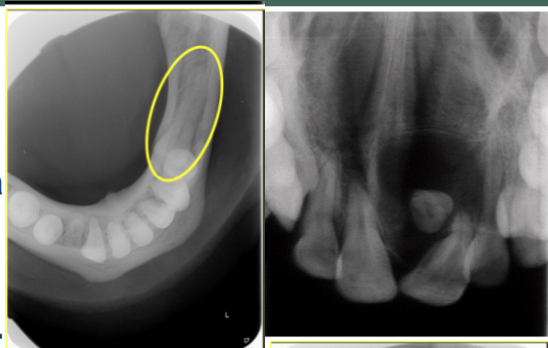

Name this type of radiograph?

Occlusal. There are 2 types: